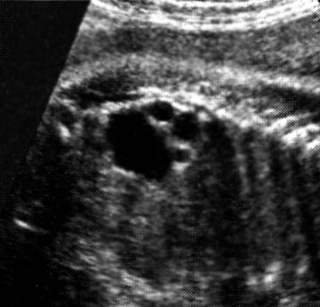

Πολυκυστικοί νεφροί ενήλικα

τύπου - Νεφρική δυσπλασία (Potter III)

Η νόσος κληρονομείται με τον αυτοσωματικό επικρατούντα χαρακτήρα και παραμένει

ασυμπτωματική μέχρι την 3η-5η δεκαετία της ζωής. Σε αντίθεση με τον εμβρυικό

τύπο, σπάνια διαγιγνώσκεται προγεννητικά. Προγεννητικά αναφέρεται διάγνωση σε

λίγες περιπτώσεις και αφορούσε σε έμβρυα με οικογενειακό ιστορικό και μορφές

που είχαν μοιραία κατάληξη στη νεογνική και σχολική ηλικία. Ένα στα 1.000 άτομα

φέρει τη μετάλλαξη του γονιδίου στο χρωμόσωμα 16. Η προγεννητική διάγνωση είναι

δυνατή με βιοψία τροφοβλάστης στο α΄ τρίμηνο, ενώ στους γονείς πρέπει να τονισθεί

ότι η φυσιολογική απεικόνιση των νεφρών προγεννητικά δεν αποκλείει την ανάπτυξη

νόσου στην ενήλικη ζωή.

Χαρακτηρίζεται από ιδιαίτερα διογκωμένους νεφρούς, με αναρίθμητες κύστεις διαφόρου

μεγέθους (εικόνες 8, 9). Το αμνιακό υγρό μπορεί να είναι φυσιολογικό ή ελαττωμένο.

Στο ένα τρίτο των περιπτώσεων παρατηρούνται κύστεις στο ήπαρ, το πάγκρεας και

το σπλήνα, ενώ στο ένα πέμπτο των περιπτώσεων συνυπάρχουν ανευρύσματα στον εγκέφαλο.

Η πρόγνωση ποικίλει, από νεογνικό θάνατο, υπέρταση (50-70%), ανευρύσματα Belly

(10-30%), μέχρι φυσιολογική ασυμπτωματική ζωή.

| Εικόνα 7. Potter II, επιμήκης διατομή. | Εικόνα 8. Potter III. | Εικόνα 9. Potter III, εγκάρσια διατομή επιμήκης διατομή. |